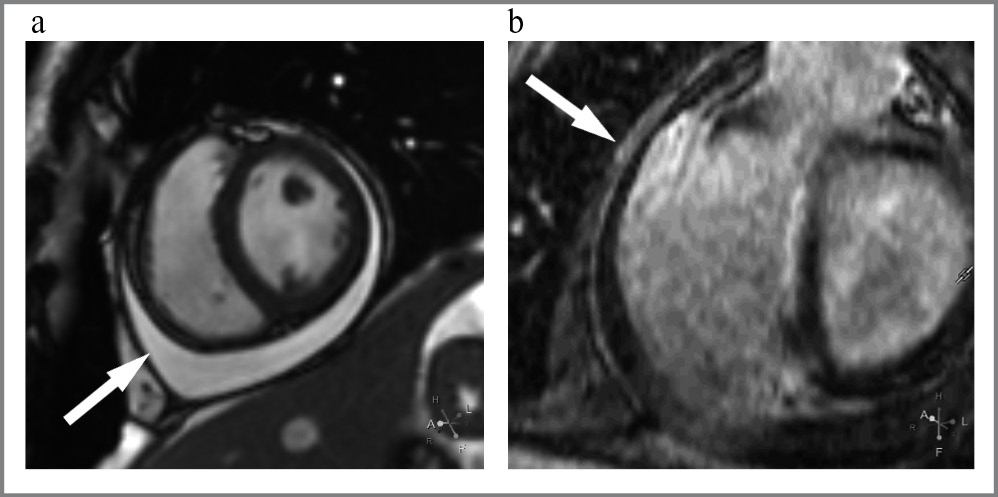

По данным кино-МРТ определялось уменьшение размеров обоих желудочков (индекс конечного диастолического объема ЛЖ = 44 мл/м2 (N = 56–80), индекс конечного диастолического объема ПЖ = 35 мл/м2 (N = 45–114). Сократимость миокарда ПЖ была в пределах нормы (48%), ЛЖ – умеренно снижена (47%). После введения контрастного препарата отмечалось его накопление в листках перикарда, наиболее выраженно оно наблюдалось вдоль правых отделов сердца в висцеральном листке перикарда. Участков патологического накопления контрастного препарата в миокарде желудочков не выявлено. Признаков отека перикарда и миокарда не обнаружено. В полости перикарда определялось повышенное скопление жидкости, максимальная толщина которого (на уровне основания сердца) – до 18 мм (рис. 4).

Рис. 4. Результаты МРТ пациента К.: a – кино-МРТ, короткая ось ЛЖ, определяется скопление жидкости между листками перикарда; b – отсроченное контрастирование, короткая ось ЛЖ. Стрелка указывает на контрастирование листка перикарда вдоль базального сегмента свободной стенки ПЖ.

Fig. 4. Patient K’s MRI results: a – cine-MRI, short axis of the LV, fluid accumulation between the pericardial layers; b – delayed contrast-enhanced MRI, short axis of the LV. The arrow indicates the contrast uptake of the pericardial layer along the basal segment of the free wall of the RV.